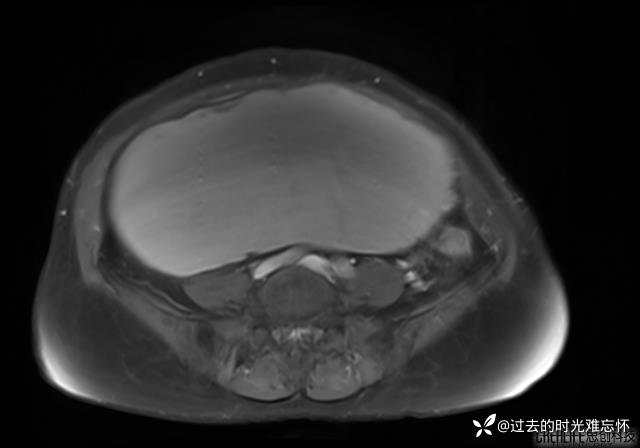

患者性别:女

患者年龄:65岁

主诉: 发现腹部隆起半年余。无其他明显不适。

浆液性囊腺瘤 (22)